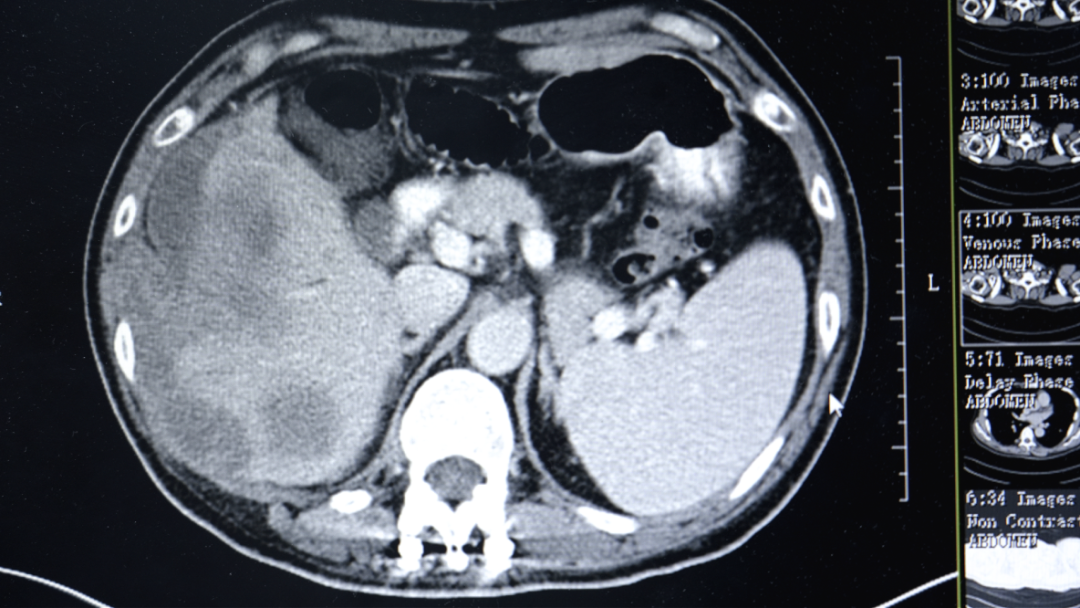

在当地医院,勇哥接受了一次介入灌注化疗栓塞术,但反应剧烈,“反复发烧,烧了足足半个月”。好不容易烧退了,复查结果却更令人绝望:肝脏病灶扩大到13.2厘米,肺转移瘤增多,肝门区、腹腔淋巴结密密麻麻。医生跟他说肿瘤扩散太广,无法手术,最多只剩“两个月时间”。

“吃了药,打了针,不怎么疼了,能吃饭能睡觉了。”几个疗程后,勇哥的生活质量明显改善。复查结果显示肿瘤得到控制,甲胎蛋白降至1.8万ng/ml。考虑到肝脏上病灶负荷太大,且紧靠周边,出血风险比较高,李红梅主任还是建议他进行肝动脉灌注化疗术(HAIC)。

第三次回院复查时,勇哥的甲胎蛋白已降至800多,CT显示肝癌及肝内多发转移瘤、双肺转移瘤及大网膜转移瘤都较前缩小,无新发病灶,病情评价为稳定(SD)。“这次做介入治疗时,医生告诉我肝上肿瘤基本没有活性了。”勇哥的声音中带着久违的轻松。